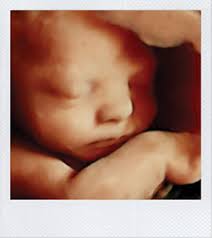

See reviews photos directions phone numbers and more for 4d Baby Ultrasound locations in Miami FL. With a 4D ultrasound you can watch your babys facial expressions and movements live. 5761 Bird Rd Suite A Miami FL 33155.

Ultrasound is South Floridas premier 3D 4D ultrasound service since 2016. Your 4D Baby - 3D 4D Ultrasound Miami. See reviews photos directions phone numbers and more for 4d Baby Ultrasound locations in Miami Beach FL.